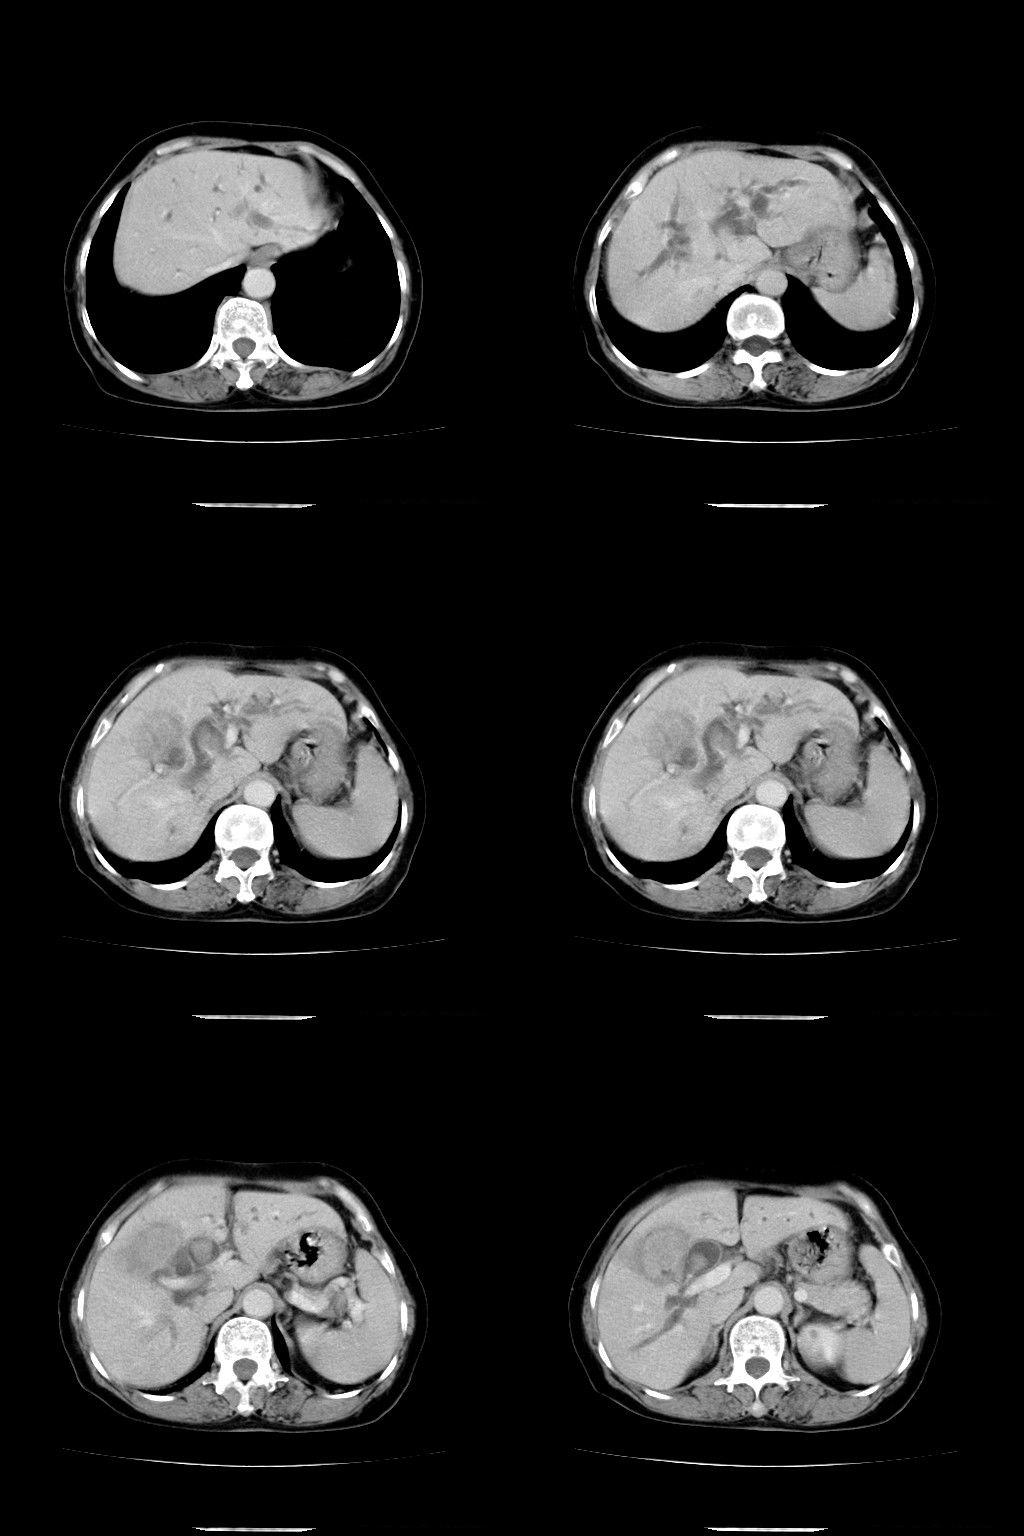

以下是引用余辉在2009-1-22 8:49:00的发言:[br]平扫肝内胆管扩张,右肝前叶球形低密度影,边缘较清楚,胆囊壁增厚,内可见较大高密度影,胆总管内亦可见高密度影,胰头区结构欠清。[br]增强动脉期见右肝前叶球形变灶明显增强,边缘见环状低密度区。胆囊见高密度影无增强,胆总管明显扩张,内见块状高密度影,周围环以低密度区,边界清楚。[br]静脉期见右肝前叶病灶持续增强,密度较动脉期增高。[br]考虑1胆囊及胆总管结石伴梗阻性胆系扩张,胆囊胆管炎。[br] 2右肝前叶占位性病变,强化规律符合胆管细胞癌,建议结合其他检查协诊